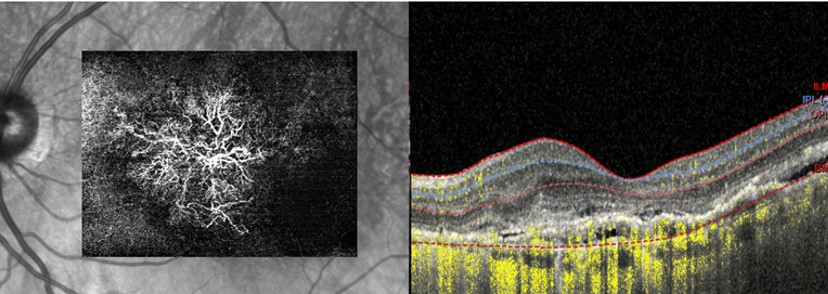

This represents OCT Angiography or OCTA. It is a major advancement on the technology of OCT. Not only can you see the cross section of the macula (on the right) but it actually will show the abnormal neovascularization (vessels responsible for exudation in exudative ARMD) as seen on the left. Not every eye care professional has this device. It is currently not reimbursed by insurance but it adds valuable information in the management of Exudative ARMD especially in patients who have persistent leakage despite multiple injections of anti-VEGF agents.